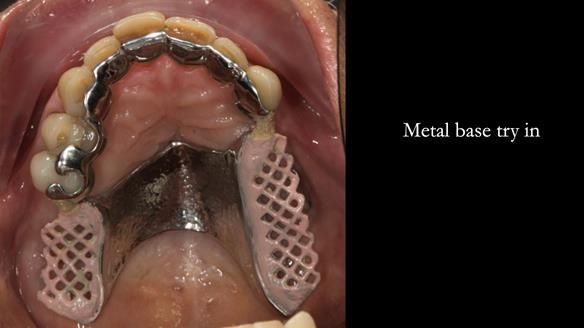

Instead, we made a Scandinavian-style, metal-based lower RPD.

It’s worth saying that the lower denture in this case was made in the early days of Rowan and me using the Scandinavian approach. Rowan cast the metalwork himself for this denture.

Looking back, we would make this denture more hygienic now. The design and finish would be more refined and delicate, particularly when compared with the upper metalwork, which was made later using Chris Hesketh’s chrome work. I will discuss this in detail at the study club.

That said, the lower denture worked beautifully. It did exactly what it was meant to do, even though, by today’s standards, it looks a little agricultural.